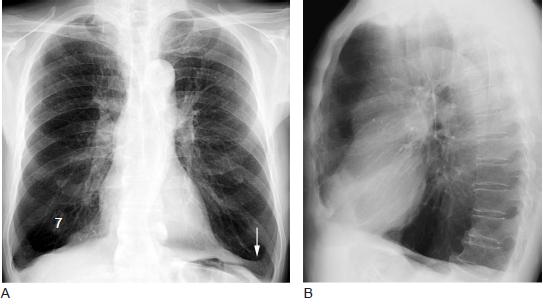

肺气肿的症状与病情轻重密切相关。早期可无症状或仅在劳动、运动时感到气短。随着肺气肿进展,呼吸困难程度随之加重,以至稍一活动甚或完全休息时仍感气短。患者感到乏力、体重下降、食欲减退、上腹胀满。伴有咳嗽、咳痰等症状,典型肺气肿者胸廓前后径增大,呈桶状胸,呼吸运动减弱,语音震颤减弱,叩诊过清音,心脏浊音界缩小,肝浊音界下移,呼吸音减低,有时可听到干、湿啰音,心音低远。